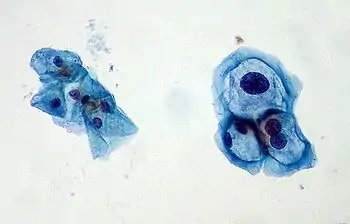

A koilocyte is a squamous epithelial cell that has undergone a number of structural changes, which occur as a result of infection of the cell by human papillomavirus (HPV).[1] Identification of these cells by pathologists can be useful in diagnosing various HPV-associated lesions.

Koilocytes may have the following cellular changes:

- Nuclear enlargement (two to three times normal size).

- Irregularity of the nuclear membrane contour, creating a wrinkled or raisinoid appearance.

- A darker than normal staining pattern in the nucleus, known as hyperchromasia.

- A clear area around the nucleus, known as a perinuclear halo or perinuclear cytoplasmic vacuolization.[2]

Koilocytes can be visualized microscopically when tissue is collected, fixed, and stained. Though koilocytes can be found in lesions in a number of locations, cervical cytology samples, commonly known as Pap smears, frequently contain koilocytes.[5] In order to visualize koilocytes collected from the cervix, the tissue is stained with the Papanicolaou stain.[5] Another way koilocytes can be visualized is by fixation of tissue with formalin and staining with hematoxylin and eosin, commonly known as H&E.[5] These stains give the cytoplasm and nuclei of cells characteristic colors and allows for visualization of the nuclear enlargement and irregularity, hyperchromasia, and perinuclear halo that are typical of koilocytes.

In LSIL of the cervix, definitive koilocytes are present. In addition, squamous cells commonly display binucleation and mitoses are present, signifying increased cellular division.[7] However, these changes are primarily limited to upper cell layers in the epithelium, no mitoses are found higher than the lower one third of epithelium, and the basal layer of cells remains a discrete layer. This differentiates this lesion from high-grade squamous intraepithelial lesion (HSIL) of the cervix.[7]